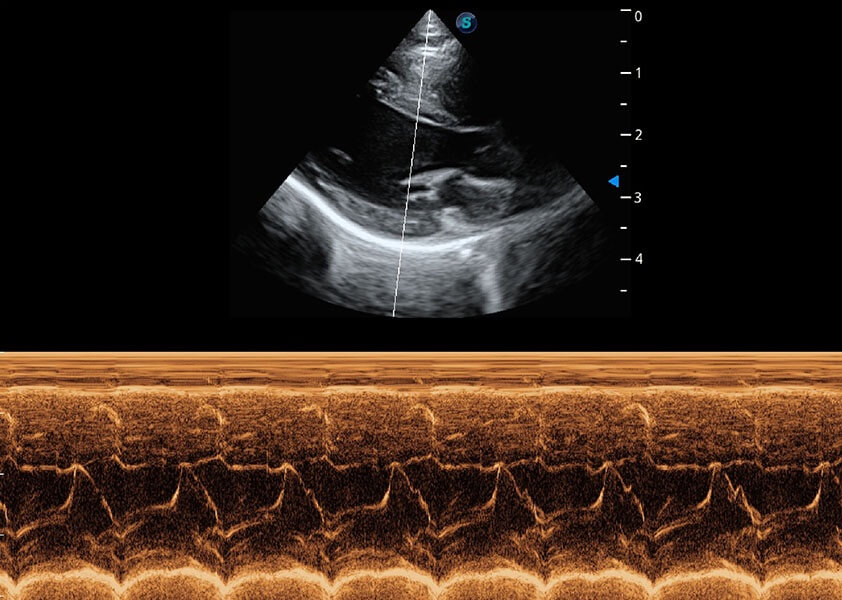

• AMM 解剖M型

通过360度任意调节3条M型取样线,在同一心动周期上观察心脏不同位置的运动曲线,得到准确的心功能测量数据,有效评估心肌运动及左心室功能。

优异的基础图像

(猫)二尖瓣M型